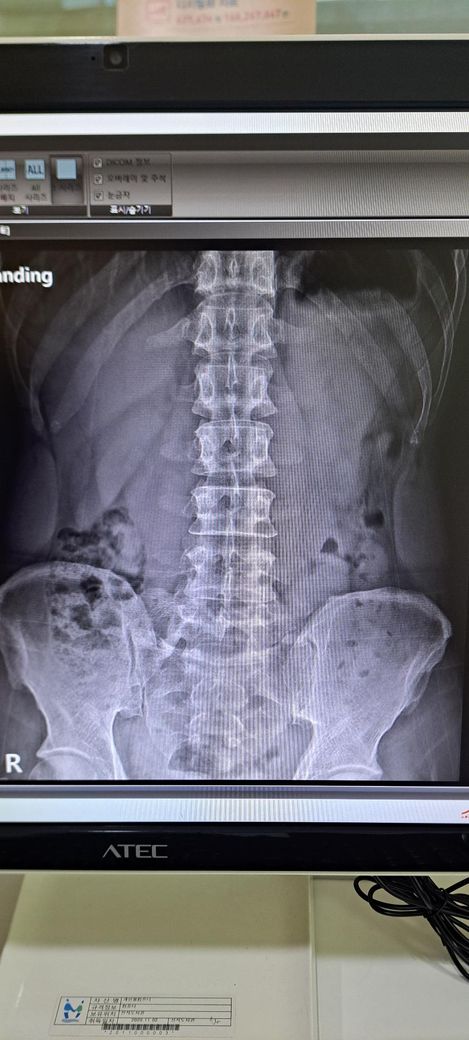

x ray 촬영한 영상인데 골반 틀어짐 및 전방경사 심각한가요? 골반 틀어짐은 어느 쪽을 교정해야 하며 골반 틀어짐 및 전방경사 교정 방법을 알려주시면 감사하겠습니다 .

사진상으로 골반 좌우 비대칭은 약간 의심되지만, 단순 X-ray만으로 "심각한 틀어짐"이라 단정하긴 어렵습니다.

전방경사 약간 있어 보이나 흔한 범위일 가능성이 크며, 스트레칭.근력운동으로 충분히 교정 가능한 수준으로 보입니다.

일단 골반 같은 경우 좌우 대칭이 다르며 약간의 전방 경사 및 틀어짐이 있는 것으로 보입니다.

정면 사진상 골반의 좌우높이 차이가 관찰되며, 이는 대퇴골의 위치변화와 연관되어 보입니다. 측면 사진에서 요추의 곡선이 다소 꺾여 있는 양상이 보여 골반 전방경사 가능성이 큽니다. 정면 영상에서 척추가 일직선이 아니라 완만한 S자 형태로 휘어있는 측만 소견이 보입니다. 심각한 수준은 아니나 지속적인 관리가 필요한 상태입니다. 측면 사진상 경추의 커브를 보면 일자목 상태입니다. 골반이 높은쪽의 근육은 이완시키고, 낮은쪽과 약해진 둔근, 복근을 강화하는 운동이 필요합니다. 전방경사 완화를 위해 장요근 스트레칭과 프랭크 같은 코어 운동이 효과적입니다. 흉쇄유돌근 스트레칭과 더불어 등 근육을 강화하여 어깨를 펴는것이 급선무입니다.

골반 틀어짐을 보면 오른쪽 골바 날개가 왼쪽보다 높이 위치한걸 볼 수 있습니다. 하지만 이 사진만으로 판단하기보다는 발끝까지 찍은 사진을 보고 왜 오른쪽 골반이 더 위로 높아져있는지를 판단해야 원인과 해결법을 판단할 수 있겠습니다.

척추측만은 의미있는 정도가 아닙니다. 저희가 20도 이상을 증상을 유발할 수 있는 측만으로 보는데 그만큼 측만이 확인되지 않습니다.

전방경사의 경우 현재 요추는 요추전만이 잘 만들어져있기 때문에 골반의 경사가 문제가 되는 상태가 아닌걸로 판단됩니다.